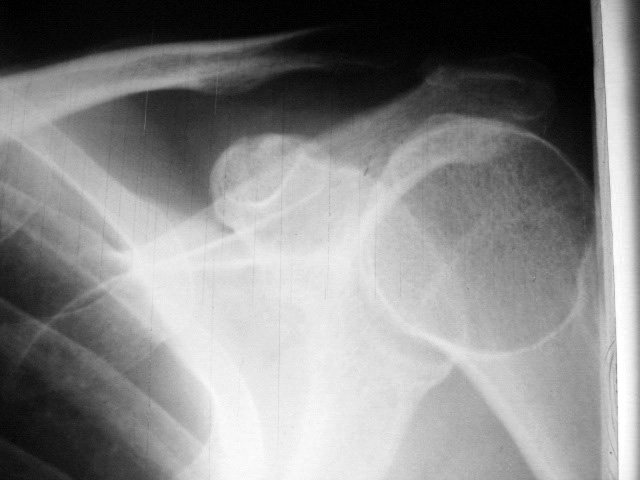

以下是引用扬仪在2008-8-15 9:51:00的发言:[br]为什么要考虑动脉瘤样骨囊肿?内骨纹清晰,无分隔,无明显膨胀改变。体检胸片,此位置前臂旋后,导致肱骨头位置不佳,为正常影像解剖变化。

以下是引用吴文利在2008-8-15 7:43:00的发言:[br]动脉瘤样骨囊肿